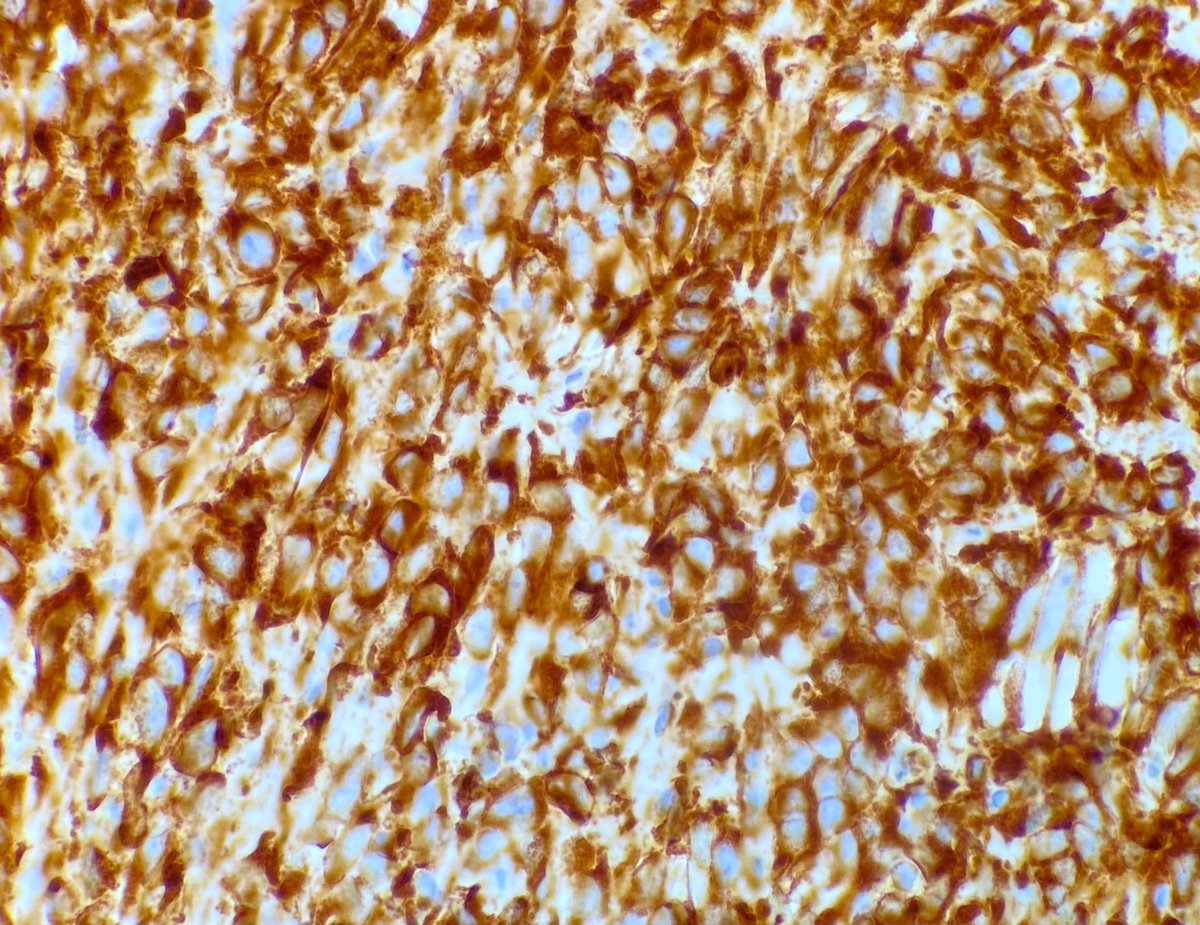

A rare sarcoma worthy of sharing. Sclerosing epithelioid fibrosarcoma. MUC4 IHC shown. First described by my mentor Dr. Meis in 1995. Her more recent study of 51 cases emphasizes its potential for aggressive behavior ➡️ journals.lww.com/ajsp/Fulltext/… #BSTpath #sarcoma

A rare sarcoma worthy of sharing.

Sclerosing epithelioid fibrosarcoma.

MUC4 IHC shown.

First described by my mentor Dr. Meis in 1995. Her more recent study of 51 cases emphasizes its potential for aggressive behavior ➡️ journals.lww.com/ajsp/Fulltext/…

#BSTpath #sarcoma